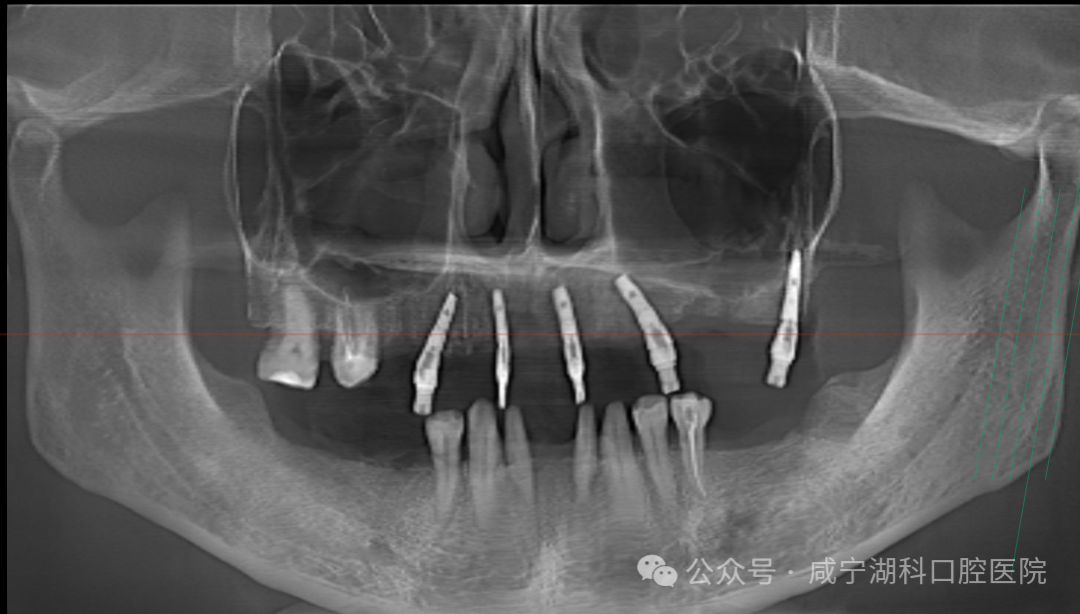

经过多方比较,1月25日,胡阿姨最终选择了刘伟院长为她进行穿翼种植,最终当天拔掉上颌两颗松动牙,保留了2颗大磨牙,植入5颗种植体,当天拔牙当天种当天戴固定牙。她说:“毕竟湖科口腔口碑很好,种植牙是很考验医生技术的手术,既然要做,就要找靠谱的、术后维护有保障的医院,技术过硬的医生。”

穿翼种植是一种特殊的口腔种植技术,被誉为种植牙界的“无土栽培术”,手术难度非同一般,临床中适用于上颌牙槽骨极度萎缩、骨量流失严重、重度缺骨等情况,无法进行常规种植牙的患者。

在这种手术中,种植体不是常规地植入牙槽骨,而是穿过上颌窦,把种植体植入到鼻部两侧的翼骨。翼状板位于上颌骨后部,较为坚固,能够提供良好的支撑。这就像是为牙齿的修复搭建了一个超级稳固的 “桥墩”,为牙列缺失或严重损坏的患者提供了一种有效的解决方案。